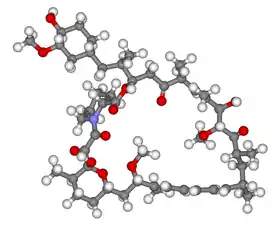

- 2002

- Several research groups investigated how the TSC1 and TSC2 gene products (tuberin and hamartin) work together to inhibit mammalian target of rapamycin (mTOR)-mediated downstream signalling. This important pathway regulates cell proliferation and tumour suppression.[71]

- 2002

- Treatment with rapamycin (sirolimus) was found to shrink tumours in the Eker rat (TSC2)[72] and mouse (TSC1)[73] models of tuberous sclerosis.

- 2006

- Small trials showed promising results in the use of rapamycin to shrink angiomyolipoma[74] and astrocytomas.[75] Several larger multicentre clinical trials began: lymphangioleiomyomatosis (LAM)[76] and kidney angiomyolipoma (AML)[77] were treated with rapamycin; giant cell astrocytomas were treated with the rapamycin derivative everolimus.[78]